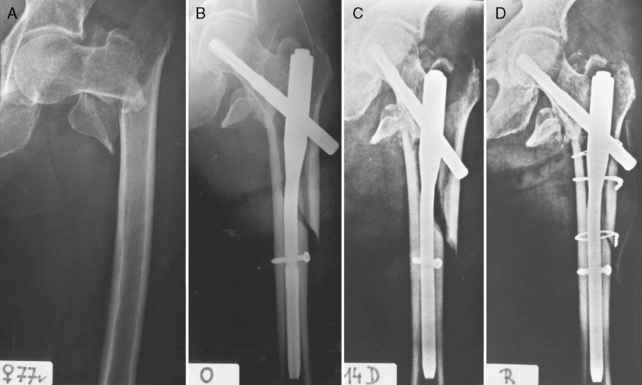

Клинический пример: Больной Ш. 66 лет. Диагноз: «Закрытый оскольчатый перелом левой плечевой кости на уровне хирургической шейки со смещением отломков». Произведена закрытая репозиция и остеосинтез проксимального отдела левой плечевой кости напряженным блокируемым спицевым остеосинтезом (рис. 11). В раннем послеоперационном периоде пациент отметил значительное уменьшение болевого синдрома. На следующие сутки после операции начата активная реабилитация. Внешняя иммобилизация не использовалась. Выписан на амбулаторное лечение на 5-й день после операции. Функция руки восстановлена через 4 недели.

Особенностью этого комплекса является то, что использование блокируемого спи-цевого остеосинтеза для хирургического лечения расширяет возможности и для реабилитации, поскольку исключает повреждение ротаторной манжеты, обеспечивает сохранение костной массы проксимального отдела плеча, исключает нарушение местного кровообращения, а также способствует ранней активизации пациентов за счет блокирования ушка Y-образной спицы. При этом процесс активной реабилитации начинается существенно раньше, чем при классическом методе Древинг — Гориневской; начальный этап лечения сокращается на 10-14 дней.

Целью нашей работы стала оптимизация лечебно-реабилитационных мероприятий после проведения оперативного лечения методом напряженного блокируемого спицевого остеосинтеза. За 2016-2017 гг. данная операция выполнена у 15 пациентов с переломами проксимального конца плечевой кости (возраст пациентов — от 37 до 87 лет). Результаты оперативного лечения оценивались по следующим критериям: некроз краев раны, воспалительные осложнения, сроки стационарного лечения и сроки восстановления функции верхней конечности с использованием шкалы DASH. Выполнялся рентгенологический контроль состояния верхней конечности в двух проекциях до и после оперативного лечения (рис. 1).